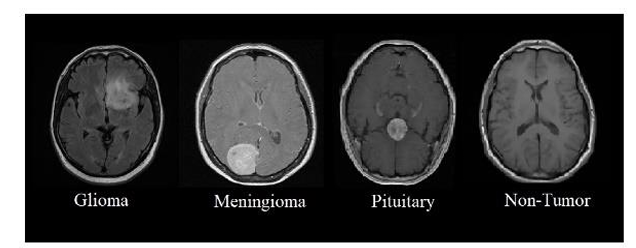

The brain, a highly complex organ with approximately 100 billion neurons and 1,000 trillion synapses, is prone to life-threatening conditions like brain tumors, caused by abnormal cell growth. In India, 28,000 cases of brain tumors are reported annually, with an alarming 86% mortality rate. Similarly, the United States anticipates 18,990 deaths from brain and CNS tumors in 2023. Brain tumors can be benign or malignant, originating either as primary tumors in the brain or secondary tumors spread from other organs. Common types include meningiomas, gliomas, and pituitary tumors, each posing severe risks due to increased intracranial pressure.

We used the publicly available Brain Tumor Detection and Classification MRI image Kaggle dataset are (https://www.kaggle.com/datasets/sartajbhuvaji/brain-tumor-classification-mri). There are 3264 brain MRI images in dataset which have been labelled as glioma tumor, meningioma tumor, no tumor and pituitary tumor. Including the number of these brain MRI images are 926 images of glioma, 937 images of meningioma, 500 images of no tumor and 901 images of pituitary tumor. The images were processed, they were divided into a training and validation set using an 80%-20% split respectively. Depending on their types and grades, brain tumor can vary in terms of size, location and shape.

fig, ax = plt.subplots(1,4, figsize=(20,20)) k = 0 for i in range(0,4): if i==0: idx=0 elif i==1: idx=827 elif i==2: idx=1649 else: idx=2045 ax[k].imshow(X_train[idx]) ax[k].set_title(Y_train[idx]) ax[k].axis('off') k+=1